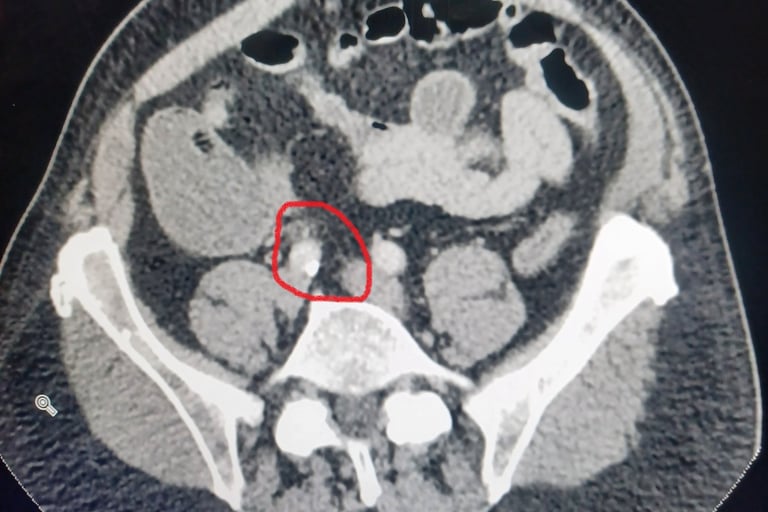

I woke in the morning and decided if I was going to get back on the road I should start eating, so I ate as much breakfast as I could. After an hour I felt worse than ever. So I decided it was time to go to the ER. By the time I got there I was actually crying. I’m not sure if it was from the pain or just relief. The doctor decided to take a CT Scan to see what was going on and offered me a some pain relief. I told him I was alone and needed to drive so he offered a non-narcotic option. I decided to hold off until we knew more. The CT Scan revealed that I had a 5mm kidney stone. At this point I asked if the pain killer worked and he said it usually did, so they injected me with something and it worked. I walked out feeling better and filled some prescriptions, one for Meloxicam, my favorite magic pill. I returned to the Hampton Inn and all that laxative started doing its job, in spades. I decided I would stay another day as my flight out Phoenix had already taken off.